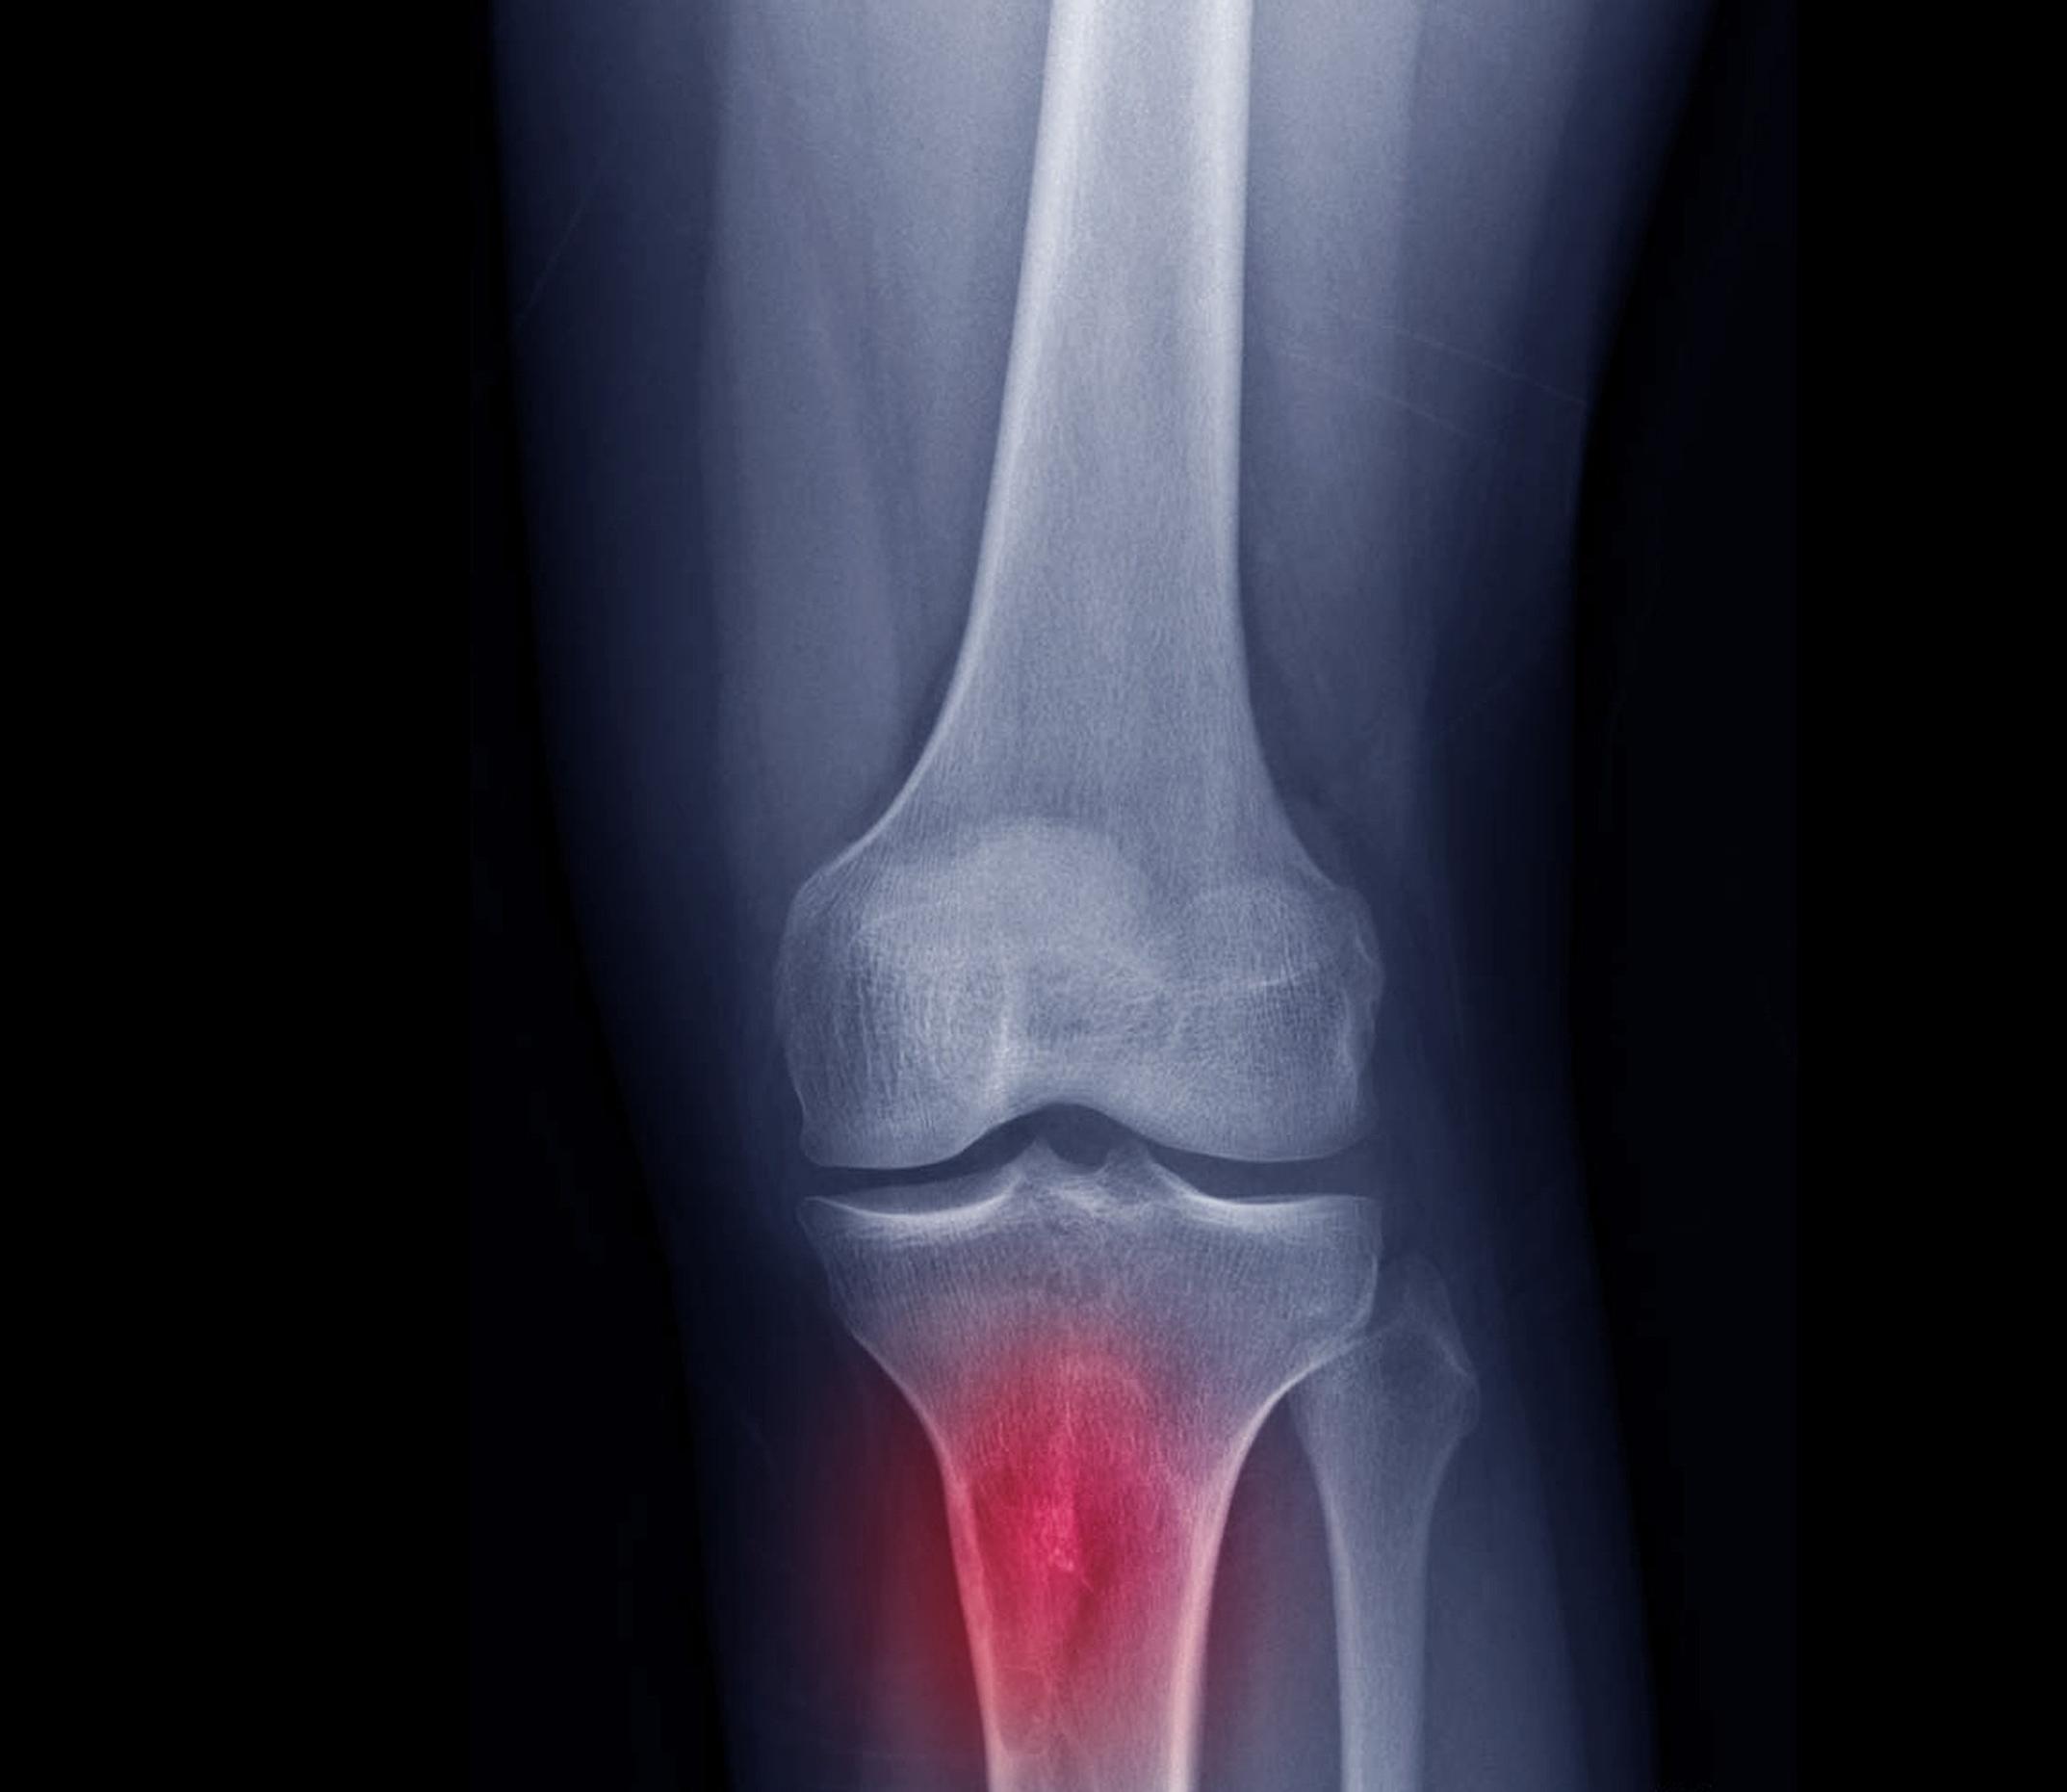

Kysta polvessa aiheuttaa yöllistä kipua – Suositeltu kyykkyjumppa vain pahentaa oireita – Mikä avuksi? Apu-klinikka vastaa

Kysymys

Kukaan ei osaa varmasti sanoa, miksi moinen, vaihtelevasti öljymäisellä nesteellä täyttyvä pussukka ilmaantuu. Joka tapauksessa siitä on yhteys polviniveleen, joten se liittynee nivelen kulumisprosessiin. Uskoisin, että nestekertymä on osa suunnittelijan tarkoituksellista oireiden lievitysprosessia, tekeehän öljyäminen kutaa rispautuneille ja kuluneille nivelrustopinnoille.

Bakerin kysta voi puhjeta

Joskus kysta voi puhjeta, jolloin siitä aiheutuu kipua kuvaamallasi tavalla. Tosin en ole havainnut, että siitä seuraisi pitempiaikaista harmia.

Lääkärille prosessi on kiusallinen, sillä tilanne simuloi syvän laskimotukoksen oireita, jolloin vaatii kokemusta erottaa ultraäänenvaraisesti repeytynyt kysta tukkeutuneesta laskimosta. Veikkaan, että aika monta kystaa on hoidettu laskimoveritulppana.

Kuten huomasit, ortopedit eivät teroittele puukkoja Bakerin vuoksi. Polven tekonivelleikkauksen yhteydessä siitä voi päästä eroon.

Kysta ei estä polviniveleen suunnattuja pistoksia (hyaluronihappo Hyalgan ja kortisoni), vaikka osa aineesta pääsee kystaan. Ainakin kortisonin tapauksessa siitä on vain etua.